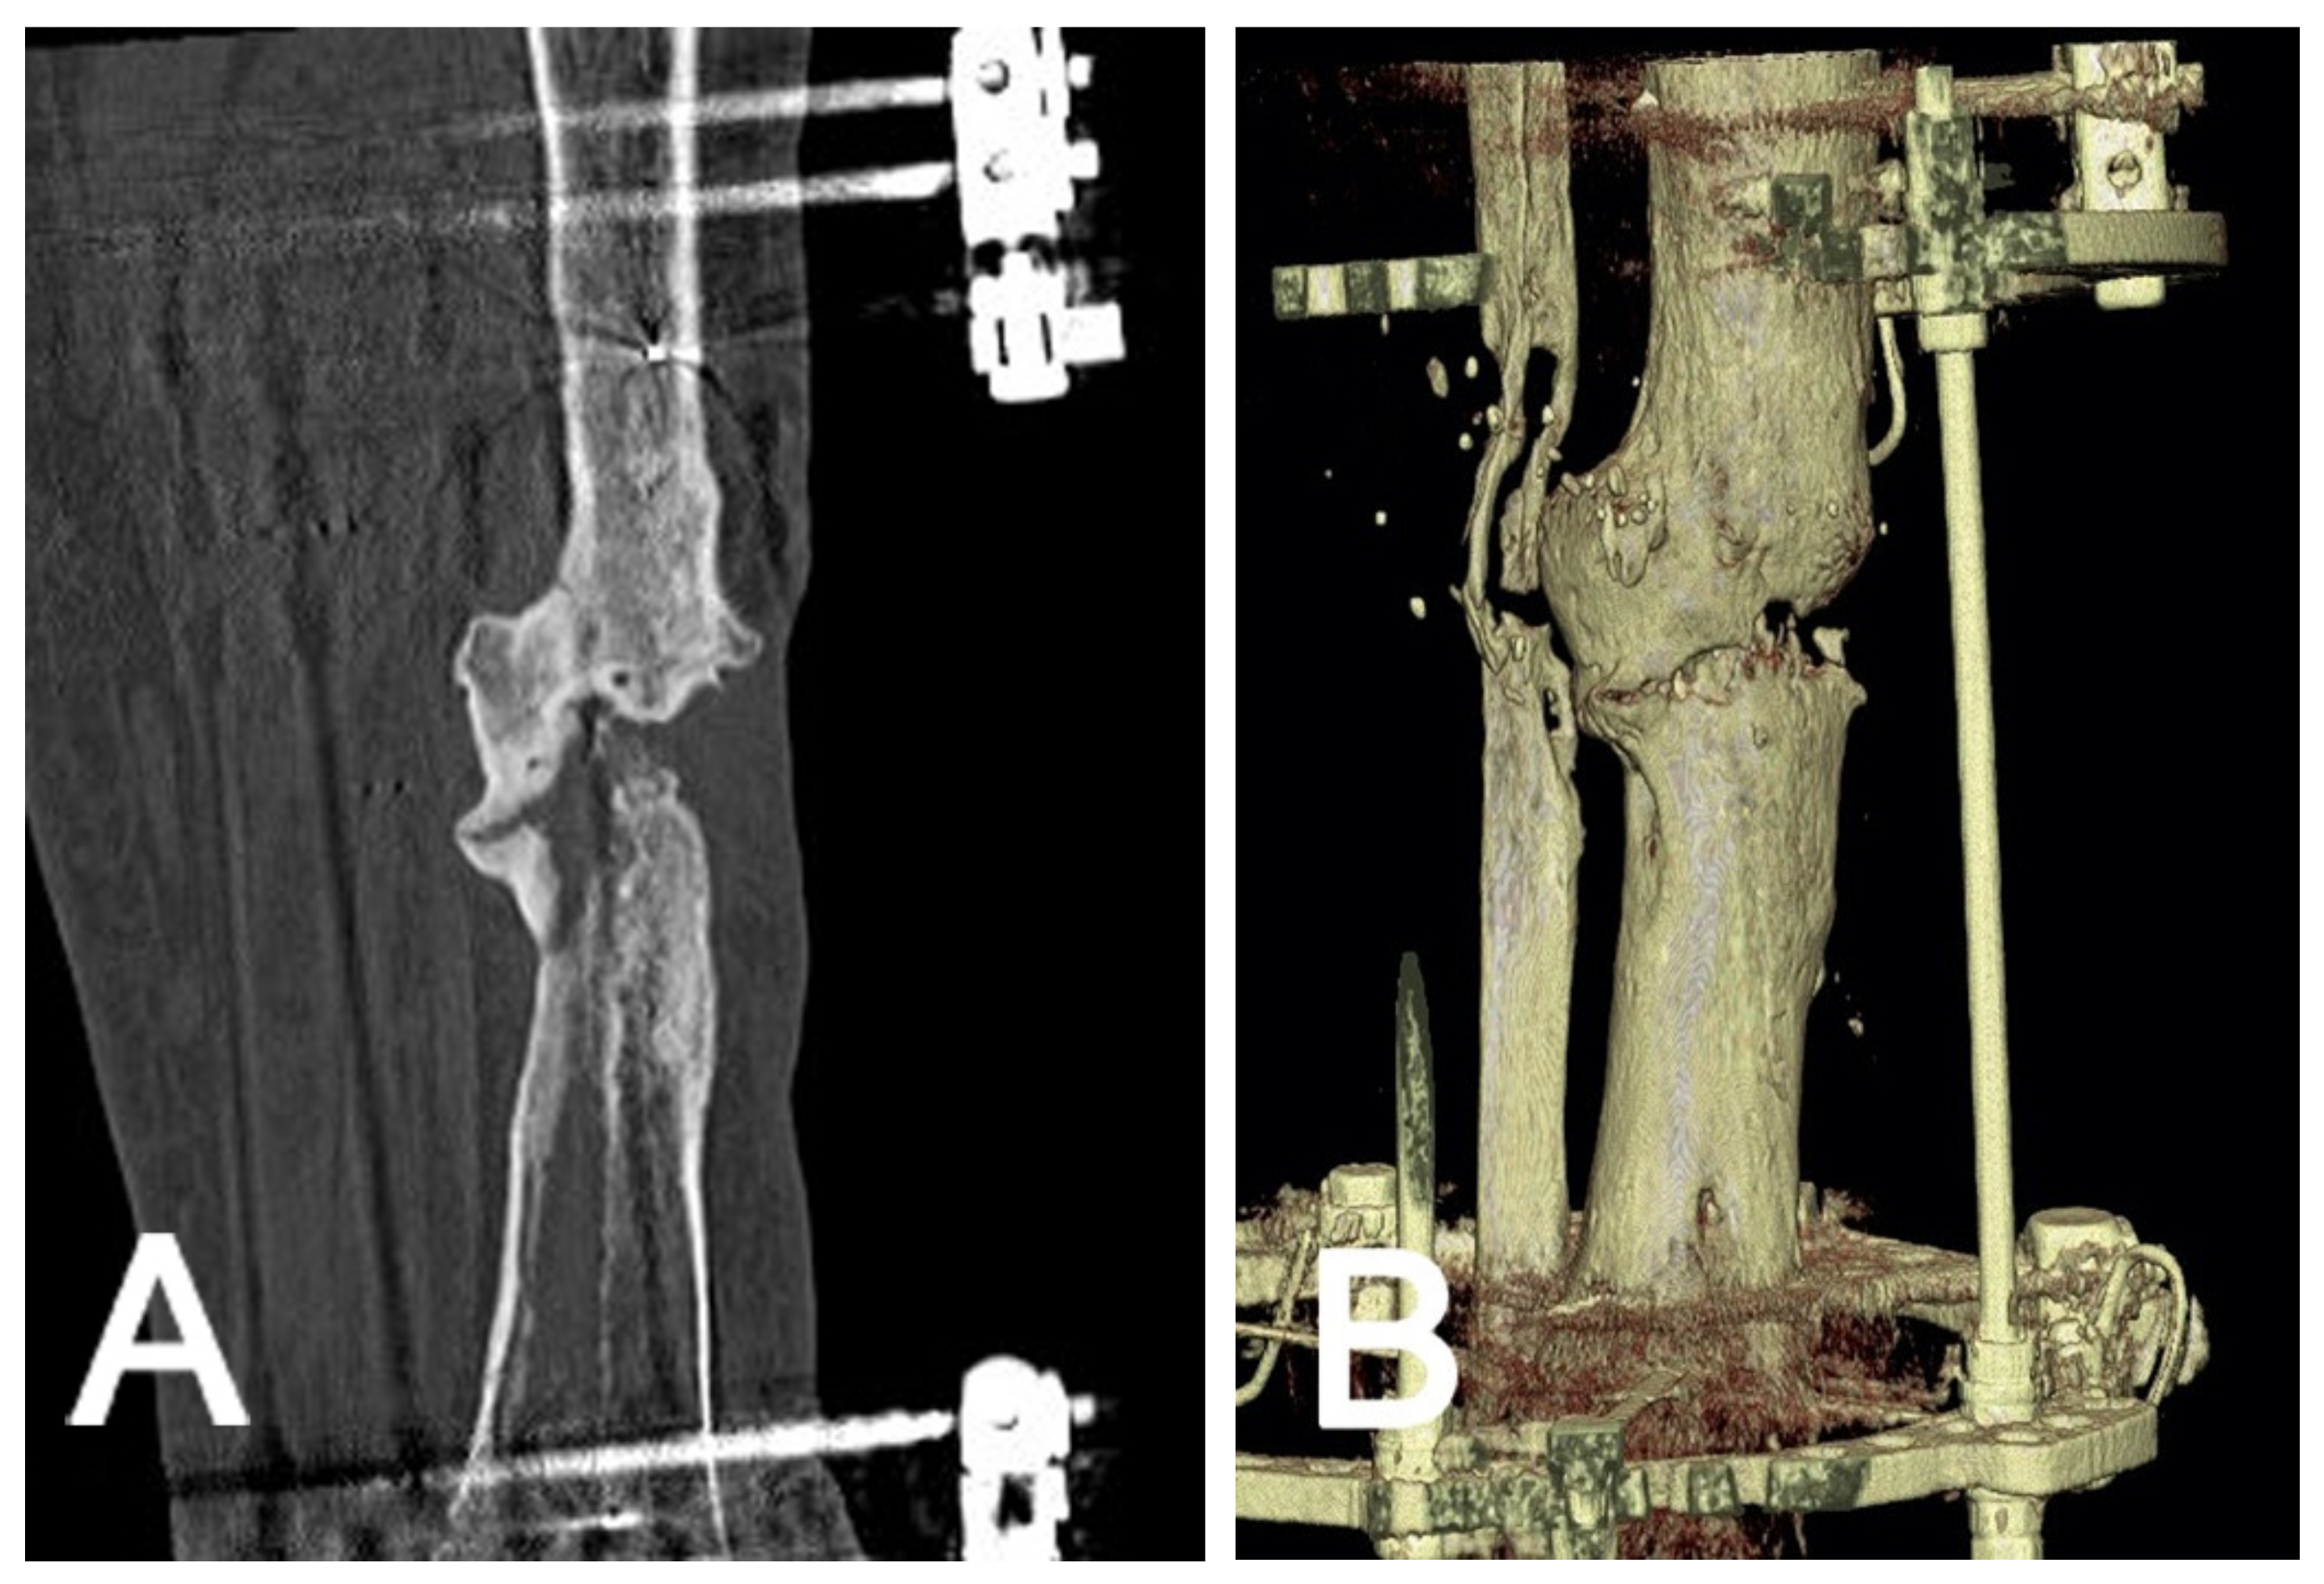

2.4.2. Non-Union Evaluation

2.4.3. Axis and Alignment